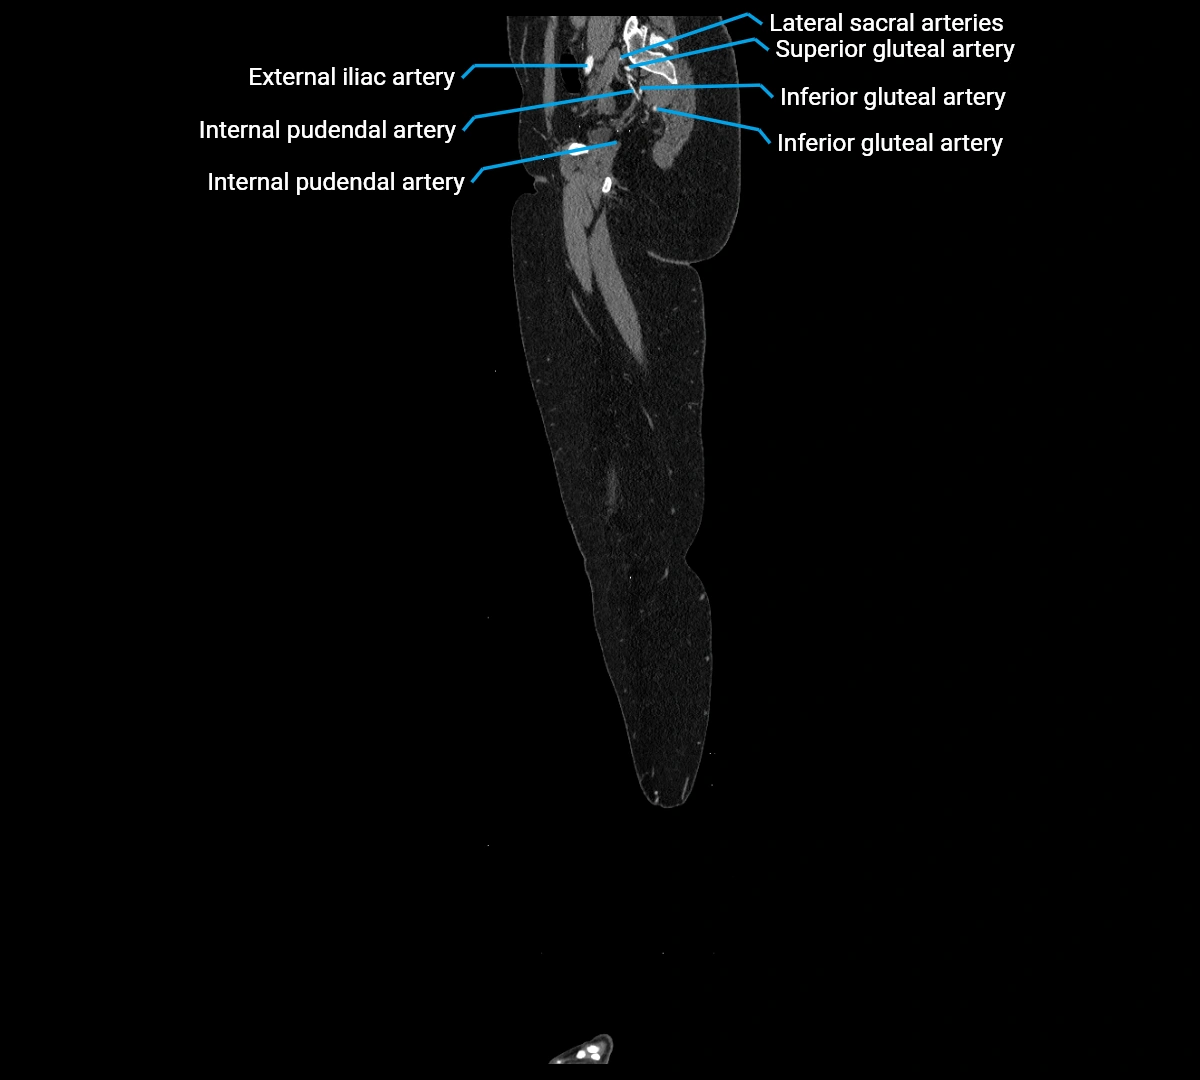

Contrast-enhanced CT (CTA):

• Gold standard for abdominal aortic imaging

• Provides excellent detail of lumen, wall, aneurysm, thrombus, and branch vessels

• Multiplanar and 3D reconstructions help in aneurysm measurement, stent graft planning, and dissection evaluation

• Detects acute rupture, traumatic injury, or occlusion with high sensitivity